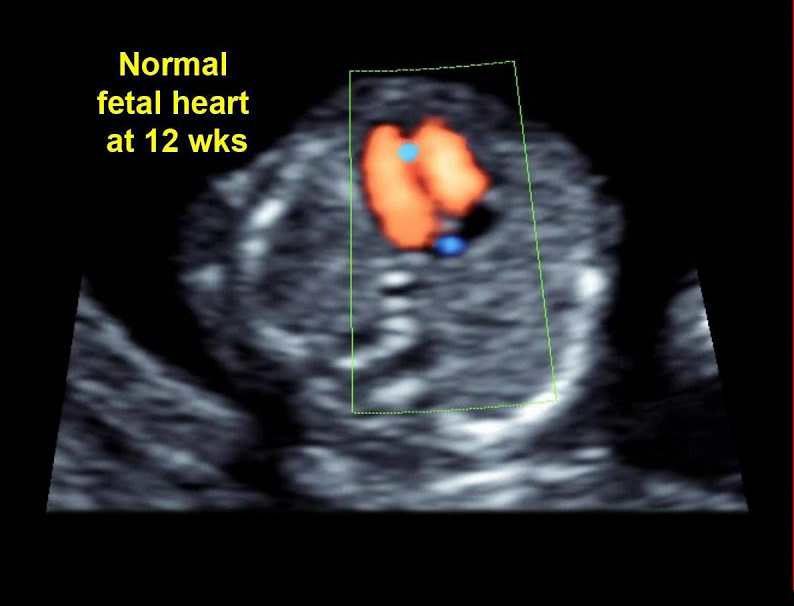

اکوکاردیوگرام جنین را می توان با اطمینان در هر زمانی پس از هفته 17-18 بارداری انجام داد. با این حال، فناوری جدیدتر از جمله مبدلهای اندوواژینال میتواند تصاویری از قلب را تا 12 هفته به دست آورد. اگر اسکن قبل از هفته 18 انجام شود، احتمالاً از شما خواسته میشود که برای دریافت تصاویر قطعیتر مراجعه کنید تا یافتههای مطالعه اولیه را تأیید کنید. در برخی موارد 18 هفته هنوز خیلی زود است.

در بیشتر موارد، اکوکاردیوگرافی مادرزادی معمولاً نتایج دقیقی را در هفته های 17 و 18 بارداری یا بعد از آن ارائه می دهد. امروزه با برخی از دستگاه های سونوگرافی مدرن، اکوکاردیوگرام را می توان زودتر، حدود 12 هفته انجام داد. با این حال، حتی پس از انجام اکوکاردیوگرام، از زنان باردار خواسته می شود سونوگرافی انجام دهند. بعد از چند هفته این کمک می کند تا اطمینان حاصل شود که نتایج دقیق تر و همچنین تشخیص سایر نقص ها خواهد بود.